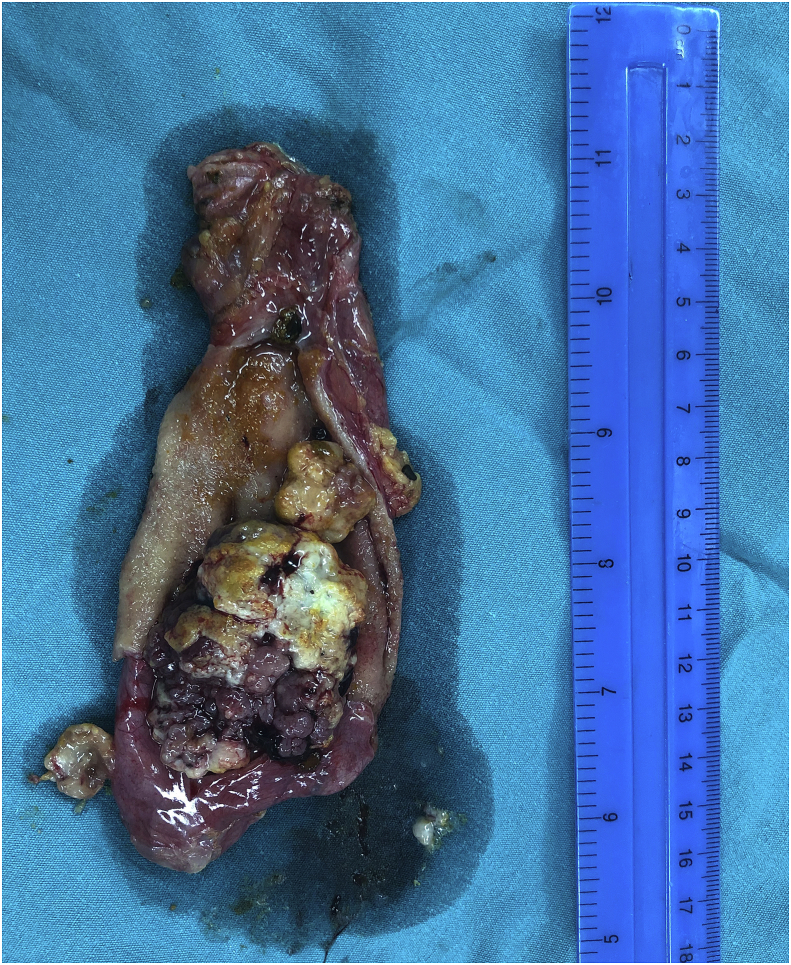

Surgery was done through right subcostal incision, cholecystectomy was performed with exploration of the common bile duct and extraction of all the stones from its lumen, T-tube was placed inside the CBD. Fig. 3.

The result of the histopathology showed dysplastic biliary epithelium arranged in tubular and papillary pattern, with no evidence of malignancy.